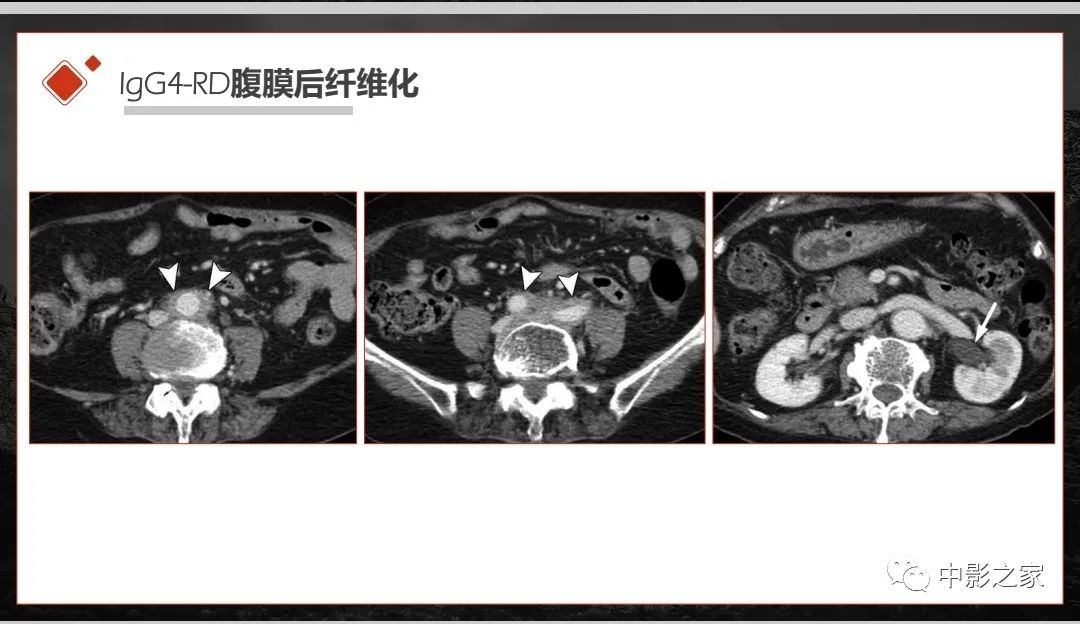

肾脏IgG4-RD临床、病理及影像特征